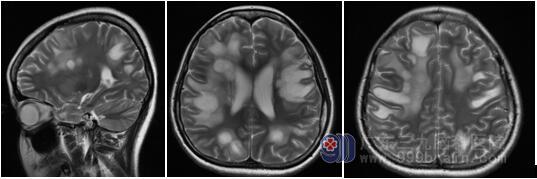

在经过激素和丙种球蛋白序贯冲击治疗后,小美的病情迅速好转起来。治疗第二天,小美的眼睛变得有神了,眼球有追踪动作,治疗第三天,手脚力量好转,治疗第四天,能遵照医生指令做动作。很快,小美就可以在家人稍搀扶的情况下行走了。复查核磁,病灶明显好转,脑里的“泡泡”逐渐消散了。

王展航主任分析:髓鞘少突胶质细胞糖蛋白(myelin oligodendrocyte glycoprotein,MOG)抗 体相关的特发性炎性脱髓鞘疾病 (idiopathic inflammatory demyelinating disease,IIDDs),有学者称之为MOG抗体介导的IIDDs(简称为“MOG抗体病”)。50%的患者头颅磁共振平扫可见T2WI上高信号的脱髓鞘病灶,成斑片状弥漫分布,边缘不清,部分病灶有中心强化。大脑半球处病灶可表现为大片状,类似急性播散性脑脊髓炎样改变,部分患者发病前一月内存在疫苗接种史,特异性抗体(MOG抗体)检查对疾病诊断意义重大。MOG抗体病大部分患者急性期治疗后预后较好,对其早期识别及诊治能让患者受益更多。